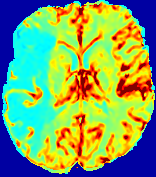

LesionRefer to captionRefer to captionRefer to captionRefer to captionRefer to captionRefer to caption𝐕rgbsubscript𝐕𝑟𝑔𝑏{\bf{V}}_{rgb}Refer to captionRefer to captionRefer to captionRefer to captionRefer to captionRefer to caption𝐕2subscriptnorm𝐕2{\|\bf{V}}\|_{2}Refer to captionRefer to captionRefer to captionRefer to captionRefer to captionRefer to captionRefer to caption3.53.53.52.82.82.82.12.12.11.41.41.40.70.70.70.00.00.0(mm/s)𝑚𝑚𝑠(mm/s)D𝐷DRefer to captionRefer to captionRefer to captionRefer to captionRefer to captionRefer to captionRefer to caption0.0200.0200.0200.0160.0160.0160.0120.0120.0120.0080.0080.0080.0040.0040.0040.0000.0000.000(mm2/s)𝑚superscript𝑚2𝑠(mm^{2}/s)Slice #1Slice #2Slice #3Slice #4Slice #5Slice #6

Figure 3: PIANO feature maps for one stroke patient, where the lesion is located in the left hemisphere. Top row: segmented stroke lesion region (white) on different slices, obtained from ISLES 2017. The corresponding slices for the PIANO feature maps are shown in the following rows.

For a better insight into an estimated velocity field 𝐕𝐕{\bf{V}} and diffusion field 𝐃𝐃{\bf{D}}, we compute the following maps: (1) 𝐕rgbsubscript𝐕𝑟𝑔𝑏{\bf{V}}_{rgb}: Color-coded orientation map of 𝐕=(Vx,Vy,Vz)T𝐕superscriptsuperscript𝑉𝑥superscript𝑉𝑦superscript𝑉𝑧𝑇{\bf{V}}=(V^{x},V^{y},V^{z})^{T}, obtained by normalizing 𝐕𝐕{\bf{V}} to unit length and mapping its 3 components to red, green, blue respectively; (2) 𝐕2subscriptnorm𝐕2\|{\bf{V}}\|_{2}: 222 norm of 𝐕𝐕{\bf{V}}; (3) D𝐷D: scalar field in Eq. 5.

Fig. 3 and Fig. 4 show the PIANO feature maps estimated from two ISLES 2017 patients: all are highly consistent with the lesion in both cases. Details of the blood flow trajectories are revealed in 𝐕rgbsubscript𝐕𝑟𝑔𝑏{\bf{V}}_{rgb} by the ridged patterns and the sharp changes of colors in the unaffected (right) hemisphere, while the flat patterns appearing within the lesion provide little directional information about the velocity and indicate low velocity magnitudes. Velocity magnitudes are more directly visualized via 𝐕2subscriptnorm𝐕2\|{\bf{V}}\|_{2}, from which one can easily locate the lesion where 𝐕2subscriptnorm𝐕2\|{\bf{V}}\|_{2} is low. D𝐷D also indicates lower diffusion values in the lesion, though with less contrast potentially due to the fact that it captures the accumulated effect of CA diffusion at the voxel-level.